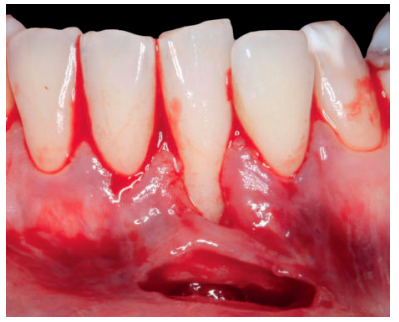

Previamente a la intervención, la paciente se enjuagó durante 1 minuto con un colutorio de clorhexidina. La técnica quirúrgica comenzó con la preparación del lecho receptor, para ello se realizó una incisión sulcular a espesor parcial a nivel de la recesión, se continúo diseccionando apical y lateralmente, extendiéndose de 3 a 5 mm de la recesión para permitir la entrada del ITC y su estabilización. Posteriormente, se realizó una incisión en el fondo de vestíbulo, dejando un puente de tejido que servirá para un doble aporte sanguíneo al injerto (Figura 2).